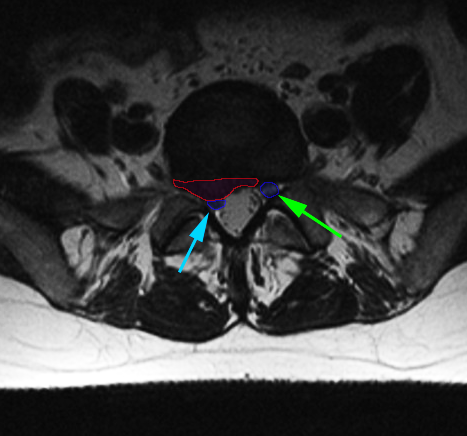

Κήλη οσφυϊκού μεσοσπονδυλίου δίσκου (κόκκινο περίγραμμα), η οποία προκαλεί στένωση του δεξιού τρήματος και πίεση στο νεύρο (κυανό βέλος). Αριστερό νεύρο με πράσινο βέλος. |